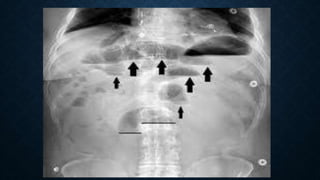

This document provides an overview of x-rays for medical students, covering topics such as ensuring x-rays are well-aligned, exposure levels, common artifacts and anatomical features, abdominal x-ray positions and views, and specialized x-rays including barium swallows, enemas, and tests to examine the esophagus, small bowel, biliary tree, and kidneys.